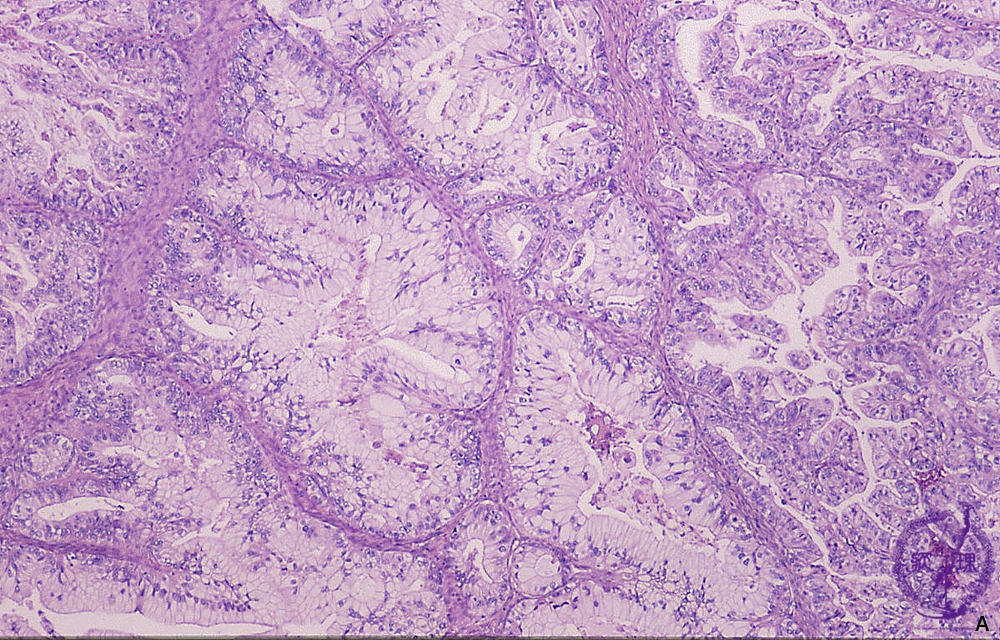

Histology (HE stain, intermediate power): Carcinoma cells proliferated in tubular structure with producing abundant mucin.